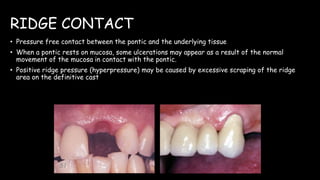

The document discusses pontic design for fixed dental prostheses. It covers pretreatment assessment of residual ridge contours, classifications of ridge deformities, surgical modification techniques, and ideal requirements for pontics. Pontic designs are classified based on their shape and materials. Factors in pontic selection include esthetics and oral hygiene. Common designs for anterior and posterior regions are described, including sanitary, ovate, and saddle pontics. Biological considerations for pontic design involve maintaining the residual ridge, abutment teeth, and supporting tissues.